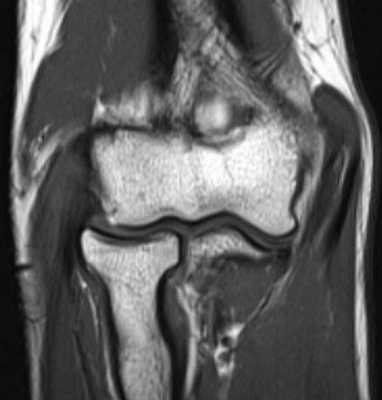

МРТ локтевого сустава в корональной плоскости. В подкожно-жировой клетчатке локтевого сустава отмечаются множественные образования неправильной вытянутой формы, местами сливающиеся между собой — вероятно, венозная мальформация.

б)МРТ локтевого сустава в корональной плоскости. Общее сухожилие разгибателей в месте прикрепления к латеральному надмыщелку плечевой кости неравномерно утолщено, МР-сигнал от него неоднородно повышен на PD FS-ВИ и Т2-ВИ за счет выраженного отека и разволокнения (признаки латерального эпикондилита), общая целость его не нарушена. Окружающие мягкие ткани с признаками отека.